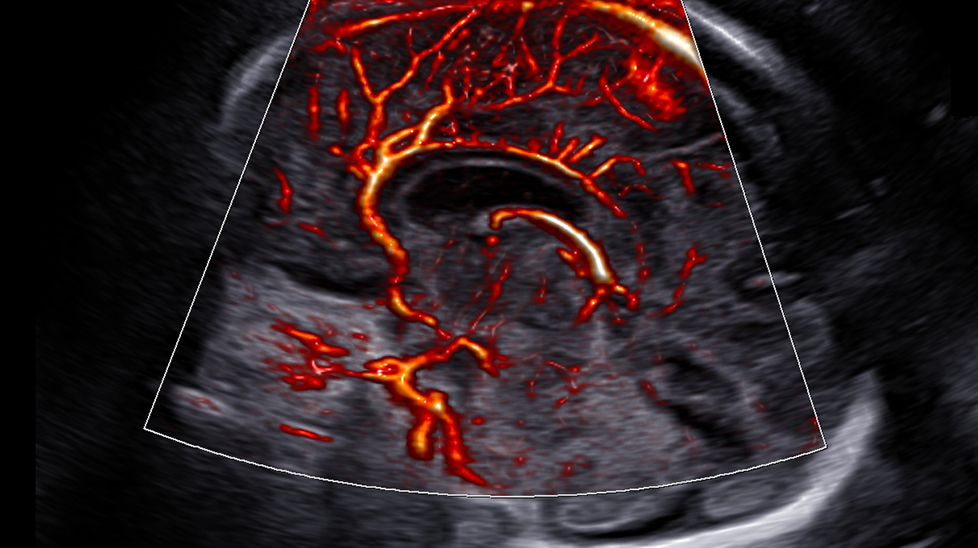

Визуализация микроциркуляторных структур с замедленным кровотоком 1 MV-Flow™ предлагает новую альтернативу силовой допплерографии для визуализации замедленного кровотока в микроциркуляторных структурах. Высокая частота кадров и усовершенствованная фильтрация позволяют MV-Flow™ получать детальное представление о кровотоке в отношении окружающих тканей или патологии с улучшенным пространственным разрешением.

на изображении: Перикаллозальная артерия с MV-FlowTM